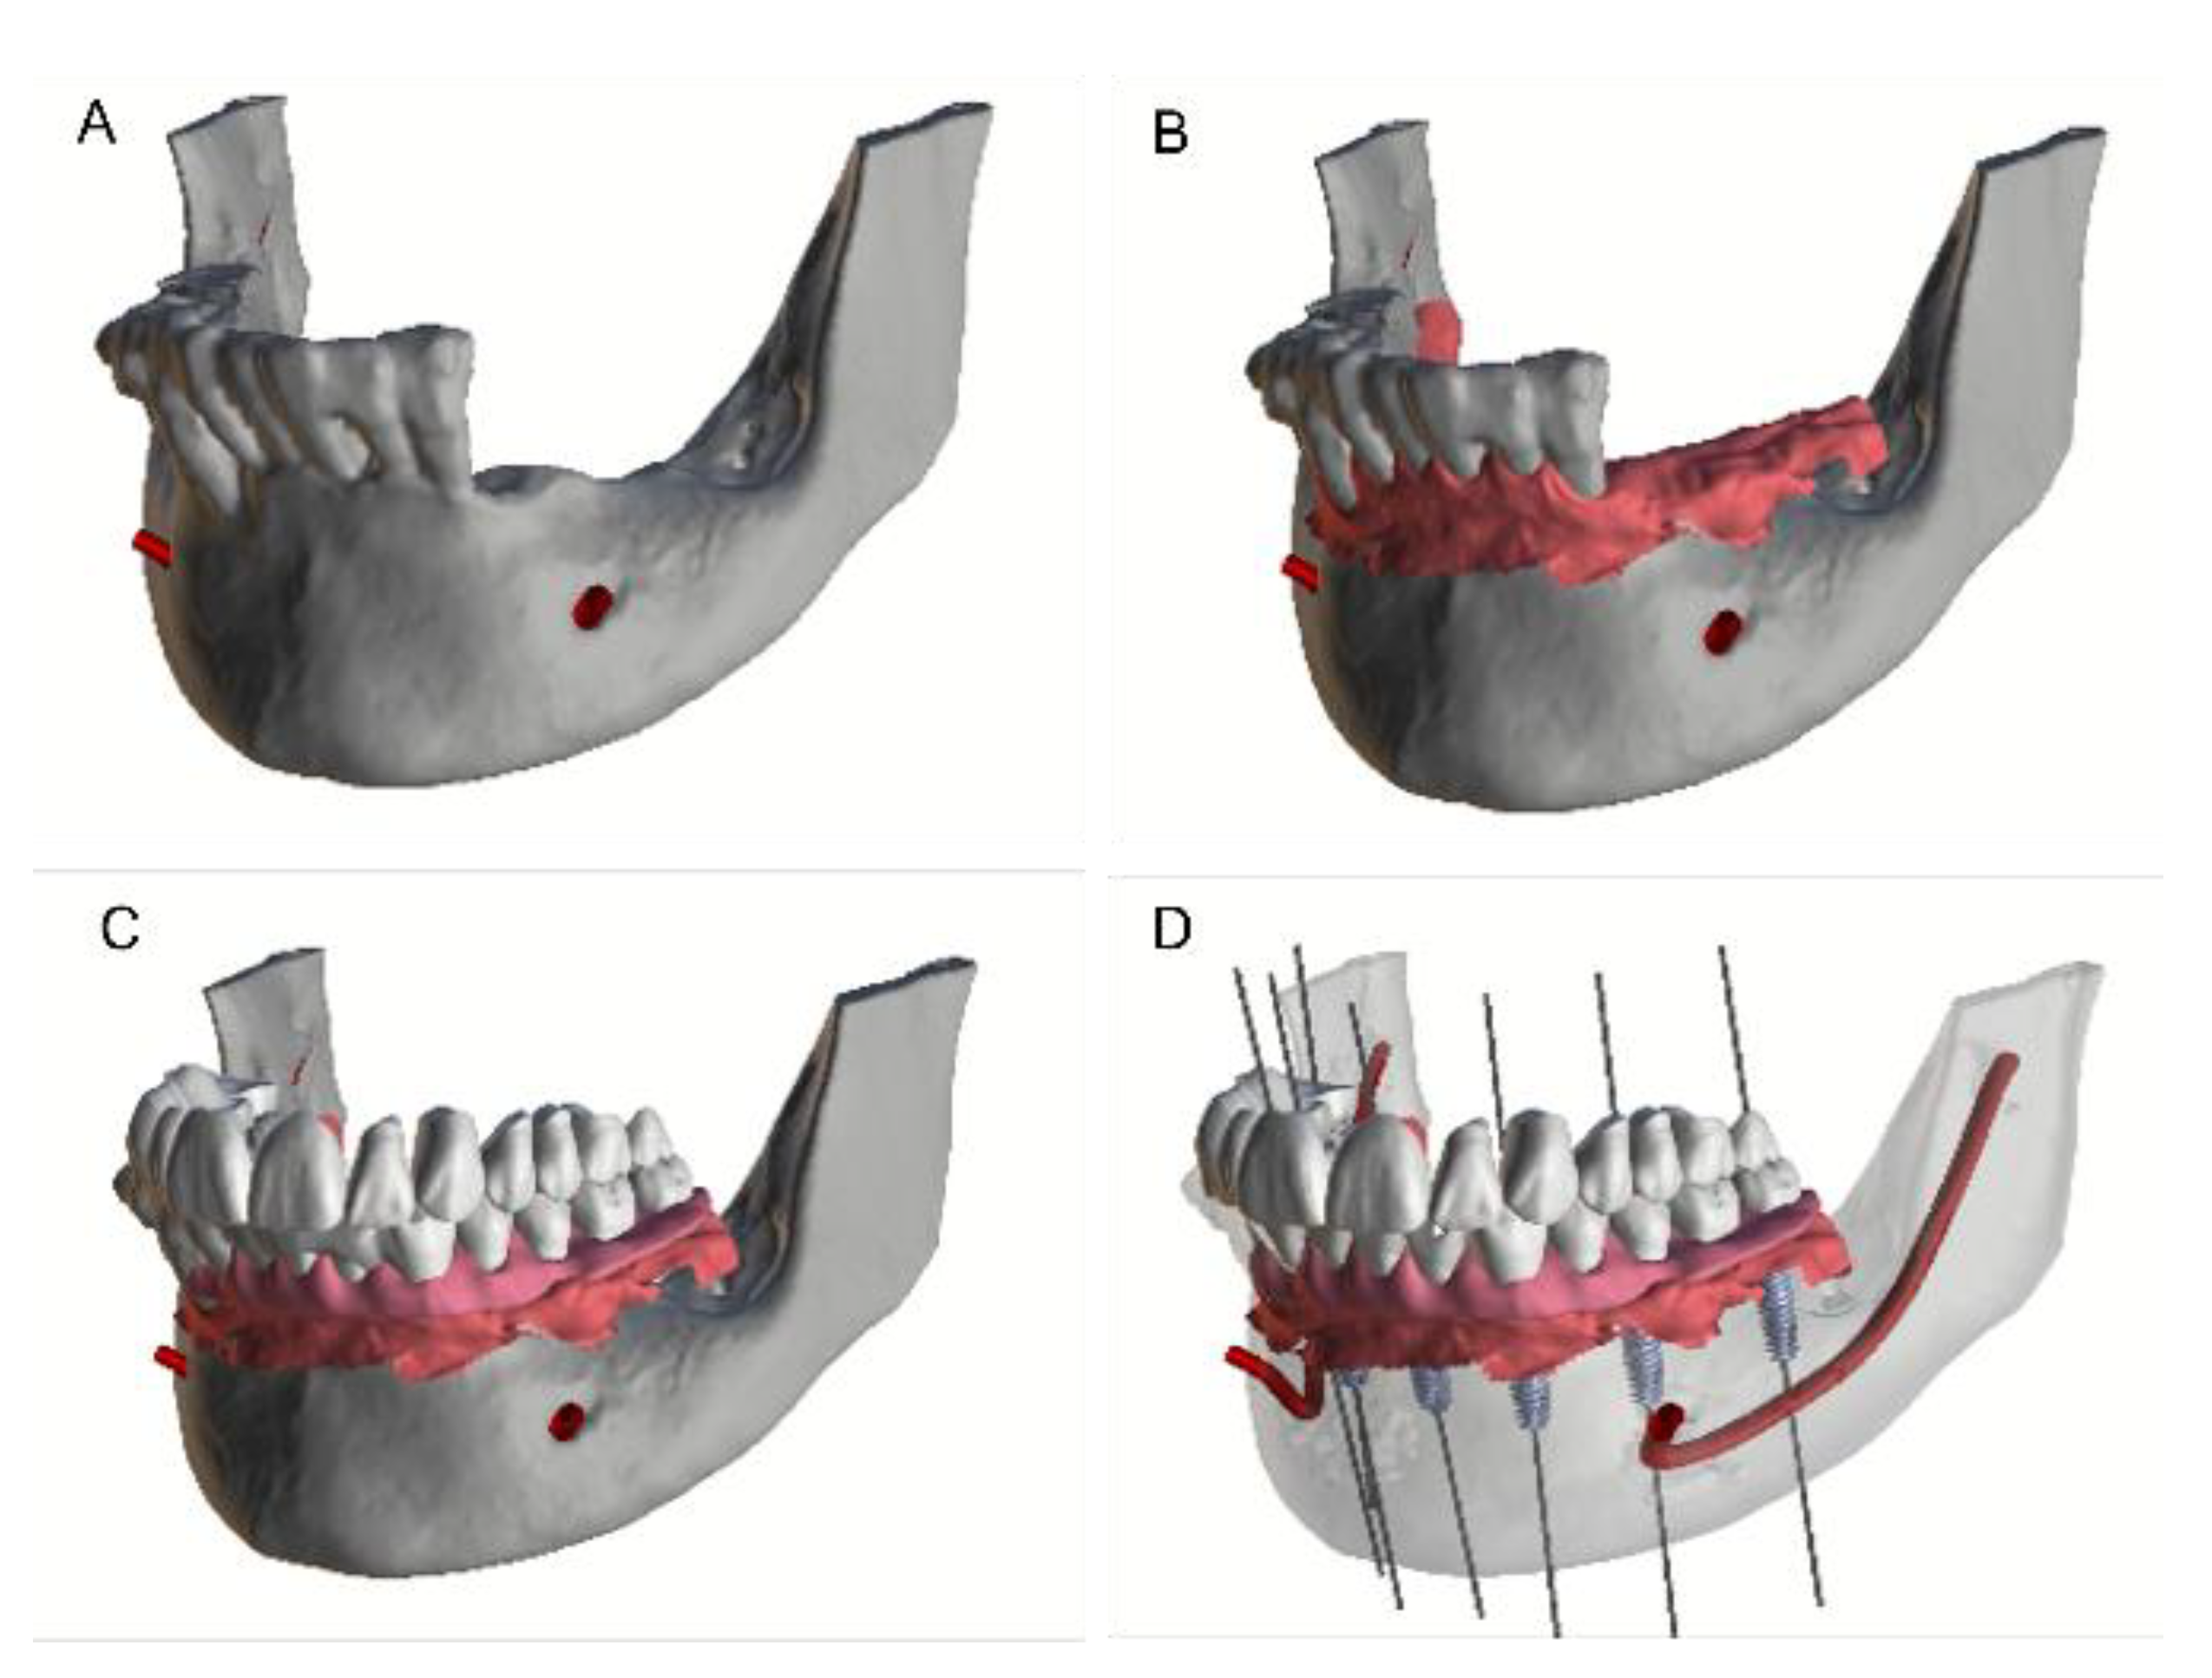

2. Materials and Methods